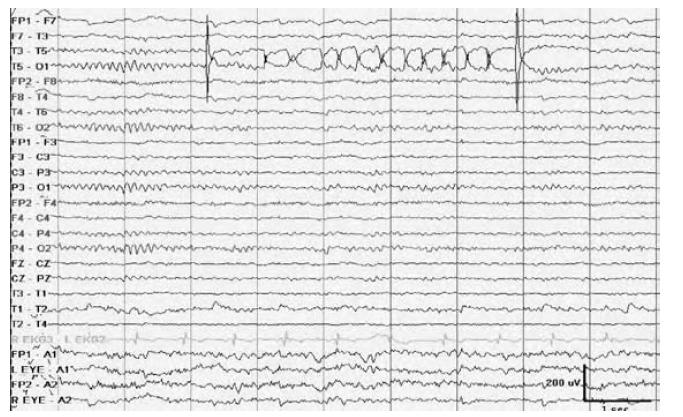

WHAT ARTIFACT IS SEEN?

Pulse artifact mimicking PLEDs at the T6 derivation. Note the 1:1 relationship to the EKG and field limited to a single electrode.